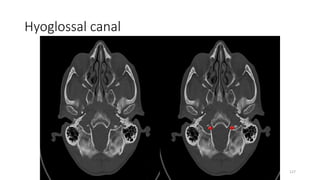

Hypoglossal canal

Content

• Hypoglossal nerve

Hyoglossal canal